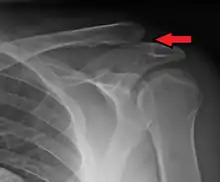

An Xray showing a separated shoulder. Notice the separation between the end of the collarbone and the scapula. | |

X-ray indicates a separated shoulder when the acromioclavicular joint space is widened (it is normally 5 to 8 mm).[8]